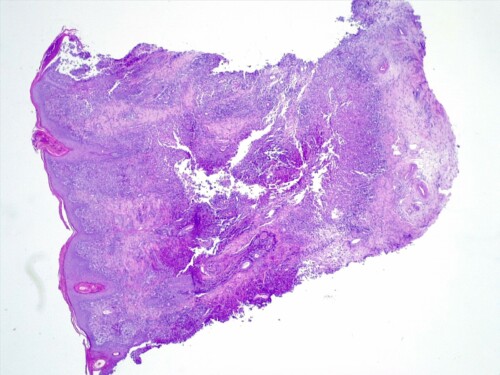

L’épiderme est atrophié, siège d’une importante hyperkératose orthokératosique, intéressant également les follicules pileux qui sont dilatés, comédoneux, avec des tiges pilaires avulsées souvent entourées d’un matériel inflammatoire mêlant granulocytes neutrophiles et des colonies bactériennes de cocci. Dans le derme, on observe au sein des unités annexielles folliculo-sébacées, une atrophie discrète des follicules pileux, des glandes sébacées et des glandes sudorales épitrichiales. Les follicules pileux sont parfois en phase télogène et catagène. La gaine conjonctive des follicules est épaissie, fibro-hyalinisée. Dans le derme, on observe de multiples foyers de métaplasie osseuse avec un derme non-inflammatoire (photos histo).